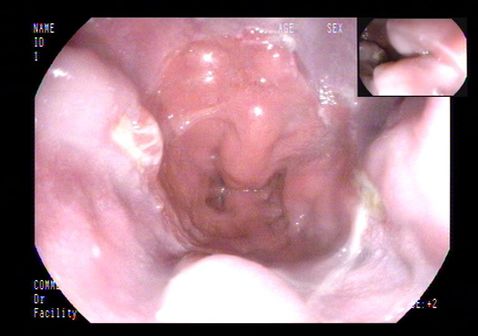

初步诊疗过程:入院后检查:血常规:单核细胞百分比 10.10%,淋巴细胞百分比 19.40%;尿常规:尿蛋白 +-;粪常规未见异常;肝功能:总胆红素 22.10umol/L,直接胆红素 12.83umol/L,谷丙转氨酶 88IU/L,谷草转氨酶 107IU/L,总蛋白 43.8g/L,白蛋白 24.3g/L,球蛋白 19.5g/L,总胆汁酸 31.4umol/L;血脂:总胆固醇 1.64mmol/L;电解质:钙 1.81mmol/L,磷 0.77mmol/L;凝血:凝血酶原时间测定 15.5秒,凝血酶原时间比值 1.46,活化部分凝血活酶时间测定 37.5秒,D-二聚体 3110.00ug/L,纤维蛋白(原)降解产物 9.56mg/L;肿瘤标志物:糖类抗原125 303.60U/ml,余项基本正常;肝炎系列+HIV+TP、T-SPOT阴性;腹水肿瘤标志物:糖类抗原125 390.10U/ml;腹水结核分枝杆菌IgG抗体阴性;复查腹水常规、生化仍提示漏出液;腹水培养阴性;PPD试验阴性;自身抗体系列未见异常。腹部超声:脂肪肝、胆囊壁毛糙、腹水;腹部血管彩超:肝段下腔静脉、门静脉及肝静脉内未见明显栓子回声。肝纤维化无创检测示:硬度值 36.5kPa。胃镜检查:食管静脉曲张、门脉高压性胃病、十二指肠多发溃疡。初步诊断为肝硬化失代偿期。给予利尿、抗感染、保肝、补白蛋白、放腹水、抑酸等治疗。患者病情无改善。

上消化道内镜: